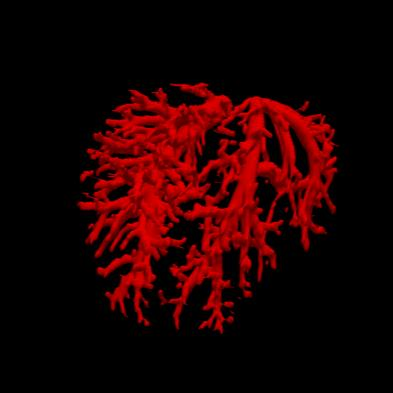

Manually segmenting the hepatic vessels from Computer Tomography (CT) is far more expertise-demanding and laborious than other structures due to the low-contrast and complex morphology of vessels, resulting in the extreme lack of high-quality labeled data. Without sufficient high-quality annotations, the usual data-driven learning-based approaches struggle with deficient training. On the other hand, directly introducing additional data with low-quality annotations may confuse the network, leading to undesirable performance degradation. To address this issue, we propose a novel mean-teacher-assisted confident learning framework to robustly exploit the noisy labeled data for the challenging hepatic vessel segmentation task. Specifically, with the adapted confident learning assisted by a third party, i.e., the weight-averaged teacher model, the noisy labels in the additional low-quality dataset can be transformed from "encumbrance" to "treasure" via progressive pixel-wise soft-correction, thus providing productive guidance. Extensive experiments using two public datasets demonstrate the superiority of the proposed framework as well as the effectiveness of each component.

翻译:将来自计算机地形学(CT)的肝脏船只人工分割,由于船只的低调和复杂形态,由于低调和复杂的形态,造成极端缺乏高质量的标签数据,因此比其他结构更需要专门知识和难度大得多。如果没有足够的高质量的说明,通常的数据驱动的基于学习的方法就会与不足的培训斗争。另一方面,直接引进低质量说明的额外数据可能会混淆网络,导致不良的性能退化。为了解决这一问题,我们提议建立一个新的、由教师协助的、有说服力的、有说服力的学习框架,为具有挑战性的肝脏船只分解任务强有力地利用响亮的标签数据。具体地说,在第三方(即加权平均教师模式)的协助下,经过变通的自信学习后,额外低质量数据集中的噪音标签可以从“阻力”转变为“压力”,通过渐进式的像素方法的软校正,从而提供富有成效的指导。使用两个公共数据集进行的广泛实验,显示了拟议框架的优越性以及每个组成部分的效能。